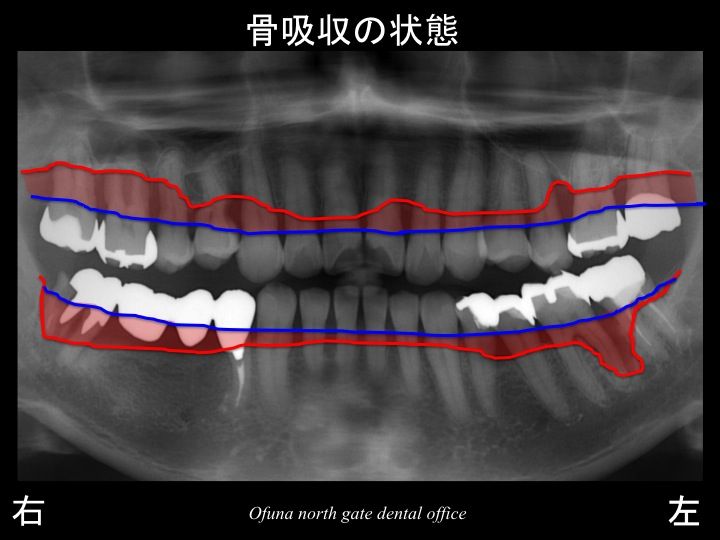

さらに わかりやすくするために、

骨吸収部位を赤色で表示します。

ここで注目したいのが奥歯です。

奥歯は骨吸収が非常に大きいのです。

奥歯は将来性が低いと言えます。

このことを考えて治療計画を立てることが重要です。

特に上顎右側の奥歯は骨吸収が非常に大きいのです。

この歯は最も将来性が低いと言えます。